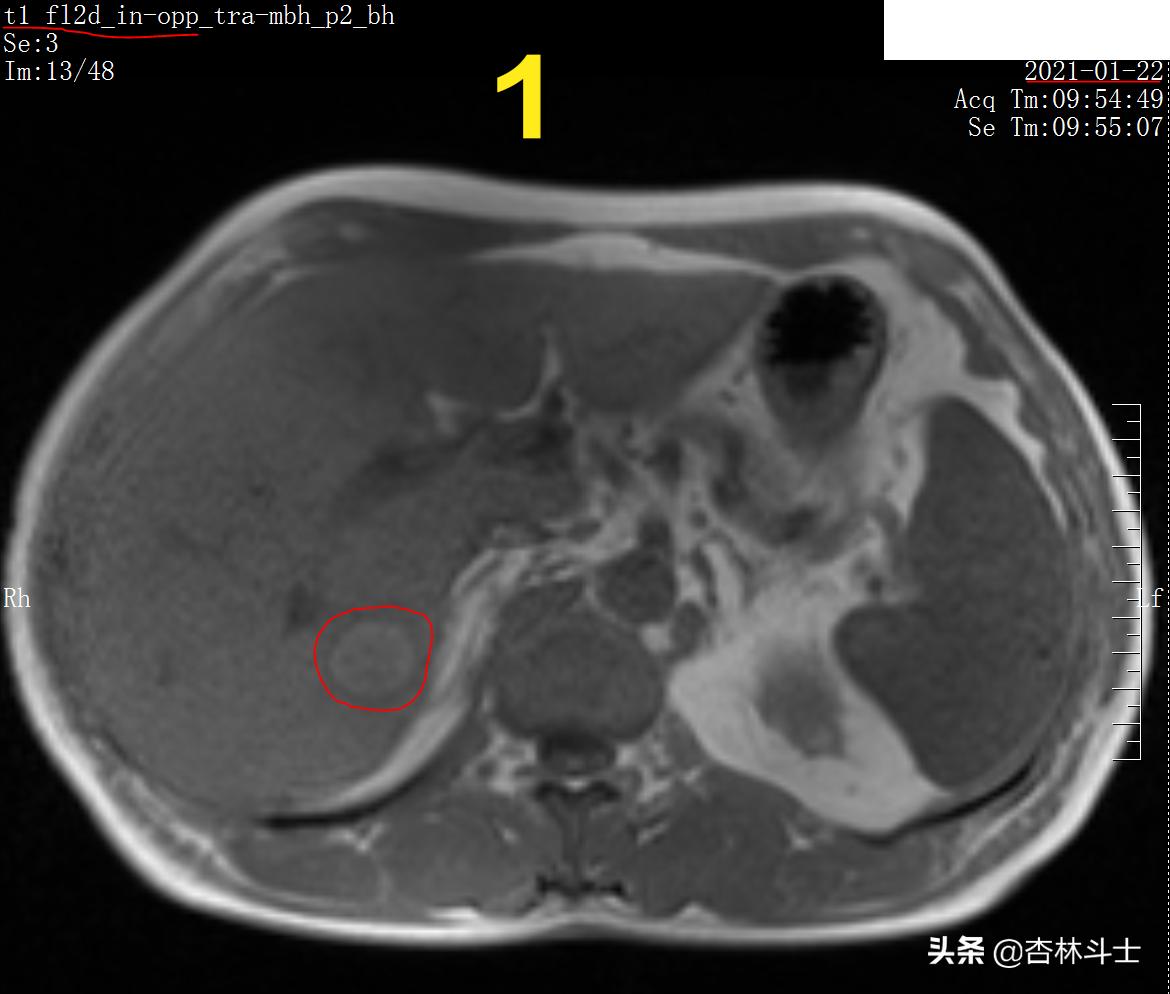

图1 T1加权同相位

图1 T1加权同相位可见肝脏右后叶近肝包膜处类圆形不均匀稍高信号影,边界清晰,边缘尚光滑。